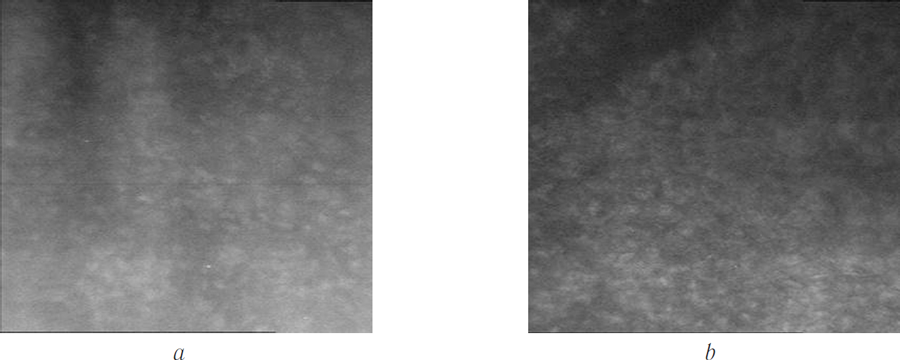

Thus, 8 of 12 patients (66.6%) with primary Fuchs ECD had a pronounced positive effect with restoration of corneal transparency (Fig. 7), complete resorption of corneal edema, appearance of endothelial cells in the DR area (Fig. 8), and significant improvement of visual acuity. The high success rate of combination therapy (DR + aCCL) in patients with primary ECD can probably be explained by the fact that a pool of healthy endothelial cells is preserved at the corneal periphery. The high density of these morphologically normal cells ensures their migration into the DR area.

Fig. 7. The restoration of corneal transparency 1,5 months after the isolated DR and ACXL (arrows indicate the border of the descemetorhexis)

Fig. 8. Confocal microscopy of endothelial cells (1503 cells/mm2) 3 months after the isolated DR and ACXL (а); confocal micro scopy of endothelial cells (1693 cells/mm2) 3.5 months after the isolated DR and ACXL (b)